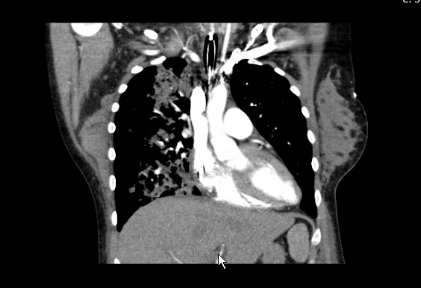

Pulmonary complication due to rituximab therapy in TTP management during pregnancy is rare but potentially life threatening for both mother and fetus. Management of severe and refractory TTP during pregnancy is challenging and requires a multidisciplinary approach. Rituximab therapy with potential serious maternal-fetal risks should be carefully chosen during pregnancy when benefits outweigh potential risks. Non-infectious lung injury should be considered among other differential diagnoses in any patient who develops respiratory symptoms or new radiographic changes while receiving this biological agent. As the symptoms are nonspecific at presentation, physicians should maintain a high index of suspicion to diagnose this complication at an early stage and start treatment to avoid severe morbidity and potential mortality (Figure 1) (Figure 2).

Figure 2 Chest CTA: Multifocal opacities most notably right upper lobe consistent with acute lung injury in the absence of pneumonia and pulmonary embolism. Small pleural effusions, right greater than left.